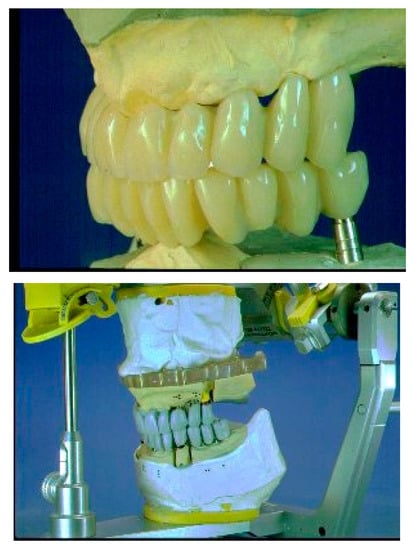

Form is the plastic image of function, and the waxings close to natural canons adhere to this concept. The functional investigation uses two practical detection methods: With the rapid facial arch, suitable for medium-complexity jobs, the positioning of the upper jaw is obtained. With the kinematic arc, the Bennet is detected in the intercondylar axis (hinge). In complex cases, the kinematic arch is used for the construction of the medium and long-term provisional, and with the diagnostic provisional the validity of the detections is verified and the TMJ behavior is checked. Prudence advises us to reduce the occlusal surfaces in order to reduce the lever arm on the implant. The modern provisional has many roles—it is the therapeutic and diagnostic name. It is in the implant prosthesis that it finds its main application, and is often underestimated (Figure 3).

The long-term diagnostic provisional is of enormous importance for the success of the final prosthesis. A design with good level characteristics must therefore be carried out: an axiographic investigation and a diagnostic wax-up on an individual articulator. In the search for the correct vertical dimension, the dentist can use the provisional to increase the vertical dimension; this method is based on the experience of the professional, who empirically determines the size. Alongside this, the radiologist and orthodontist determine on the basis angles and vertical dimension at different schools. The presence of any contractures determines a joint problem. During the medical history, the clinician will check the state of muscle tension, and a palpation to the muscles assigned to the occlusion will verify the pain. In the presence of problems at the A.T.M. before definitive rehabilitation, the clinician may decide to make small corrections to the occlusion; increase or decrease the vertical dimension; create guides; and bring the condyles back to the centric position, guiding the occlusion with an incisive canine guide and eliminating harmful contacts. The provisional diagnostic is responsible for the investigation and the functional verification before the definitive rehabilitation that will duplicate and follow it. Only after having ascertained the correct biomechanical functioning of the temporary bridge can the final ceramic metal girder of the occlusal line be realized [32,33].

Figure 3. Occlusal line and test on articulator.